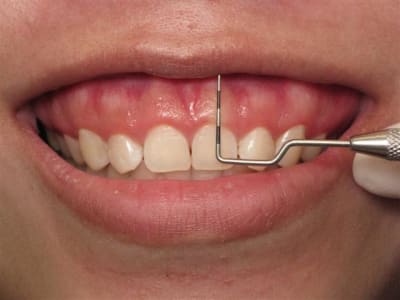

C'est une bonne technique.

Mais je pense que tu aurais pu aller un peu plus loin distalement. Aussi, les sutures semblent grosses et la soie n'est pas le meilleur matériel, trop de bactéries.

J'aime bien le Polypropylene.

Photo d'un cas similaire

Il y a plusieurs trucs que je ne comprends pas dans ce raisonnement, si tu ne fais pas une incision intra-sulculaire c'est pour ne pas avoir de récession surtout sur ta ccm.

Hors, tu as un cas qui ne demande que ça. En effet il semble que les dents soient légèrement "impactées" et le ratio longueur/largeur est inesthétique, surtout avec un sourire gingivale.